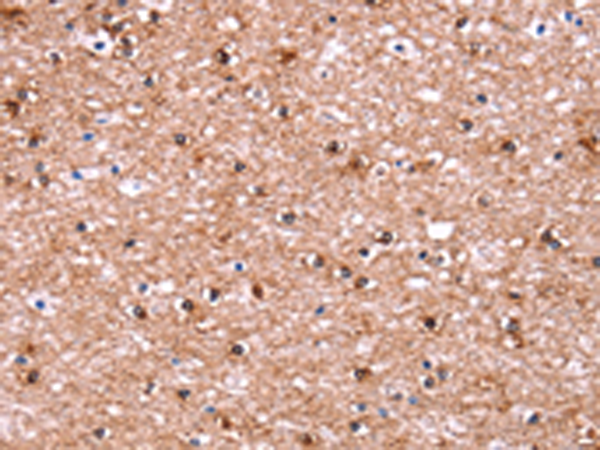

分类: 科研抗体货号: P10666别名: ADTG; CLAPG1应用: IHC反应种属: Human, Mouse